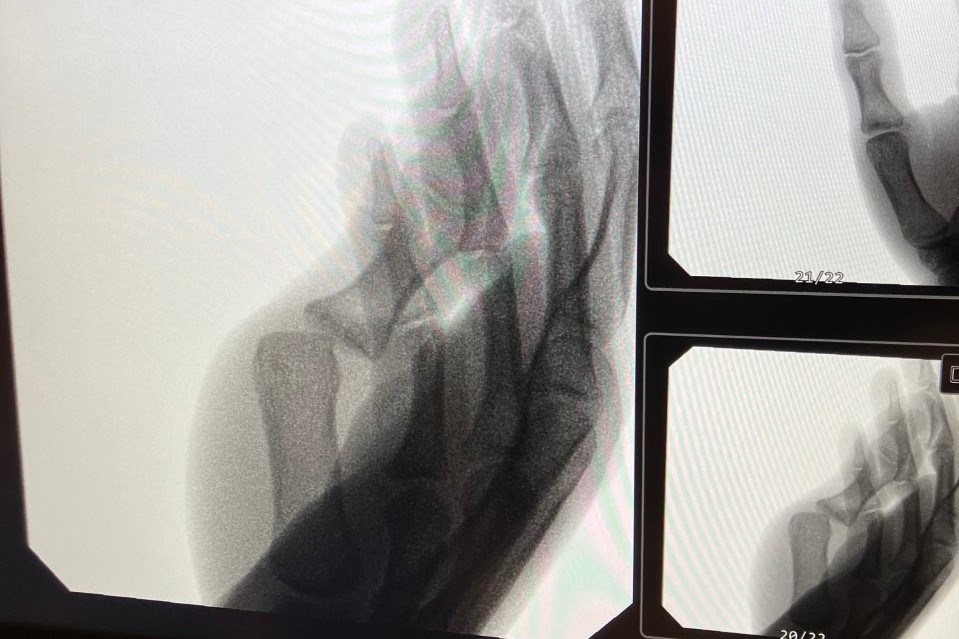

Vad tar vi med från veckan som varit... Mr T´s tumme! Något spända skinkor i matchen i söndags också. Men vi fortsätter kämpa, hela vägen. Men det är inte lätt att springa med spända skinkor. Löpningen är inställd på grund av snö, så ta ett styrkepass och skotta hemma och hos några grannar. Måndag: 17:00-XX:XX Snöskottning Tisdag: 20:00-22:00 Attarpshallen OBS, START 20:00!!! Torsdag: 19:30-21:00 Attarpshallen Fredag: 19:00-20:30 Attarpshallen Söndag: GAMEDAY IFK Bankeryd - Halmstad, Samling 13:45 Attarpshallen Herrlag/Junior lag(födda 2008-uppåt) 21 nov 2022 0kommentarer